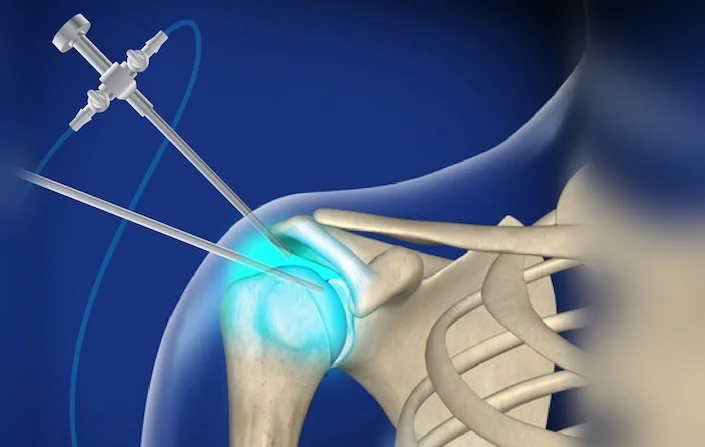

Αρθροσκόπηση ώμου στους αθλητές: Ο Ρόλος της Επέμβασης και της Αποκατάστασης για Επιστροφή στη Δράση

Η αρθροσκόπηση ώμου αποτελεί μια ελάχιστα επεμβατική χειρουργική μέθοδο, ιδιαίτερα...